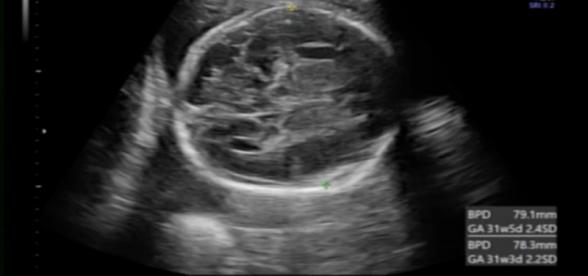

28w3d

BPD 79.1mm

AC 232.2mm

FL 49.8mm